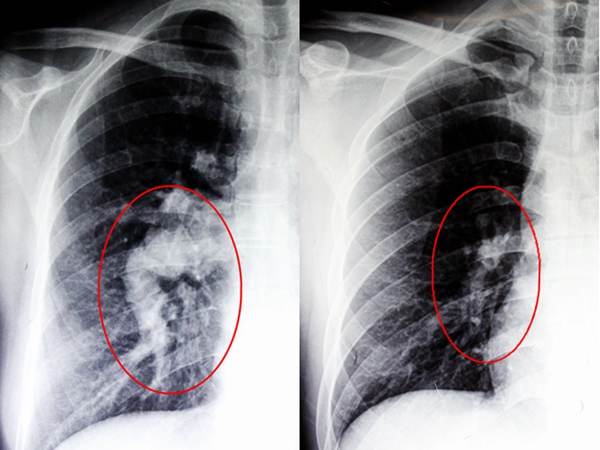

来到南宁的一家医院检查,发现邓女士的先天性心脏病-房间隔缺损已经导致肺动脉高压达到一个非常可怕的临界值,这个肺动脉高压的值再往上走,就会彻底丧失手术机会。正常的肺动脉压不超过30mmHg,平均压不超过20mmHg,邓女士的居然高达126mmHg。对于这家医院而言,邓女士的状况已经超出了他们的手术能力范围。无奈之下,邓女士只好再次踏上求医征程,经朋友介绍,来到广西中医药大学附属瑞康医院心胸外科治疗。

经过详细的心室造影和B超等各项目的检查,确定了邓女士的病情为“Ⅱ孔上腔型房间隔缺损、重度三尖瓣关闭不全、重度肺动脉高压”,瑞康医院心胸外科的专家们认为她具备手术指征,可以进行手术。在入院一个月后,经过精心的调理和周密的术前准备,邓女士顺利完成历时4个小时的手术,安返病房。